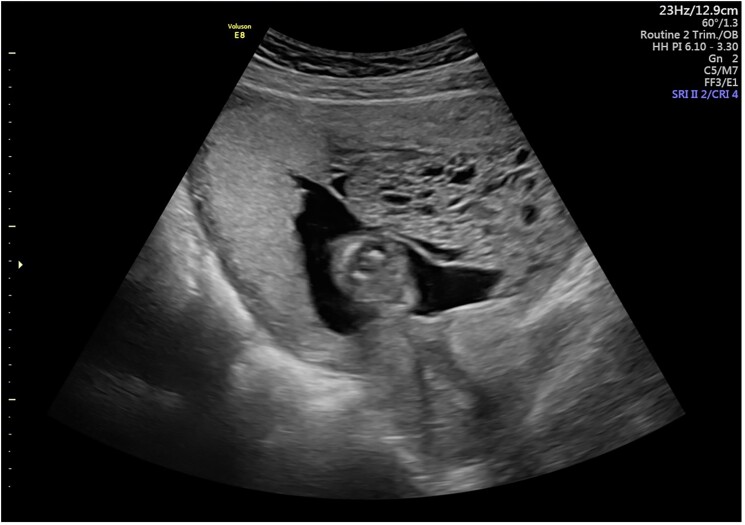

Hyperthyroidism in twin pregnancies involving a hydatidiform mole and a coexisting live fetus is a rare condition requiring careful management. We present a 34-year-old pregnant woman at 12 weeks' gestation with severe nausea, vomiting, and mild vaginal bleeding. A transvaginal ultrasound revealed a dichorionic diamniotic twin pregnancy with 1 normal fetus and 1 hydatidiform mole, leading to hyperthyroidism from elevated β human chorionic gonadotropin levels. Conservative management without antithyroid medications, combined with regular monitoring, allowed the pregnancy to continue to term, resulting in the delivery of a healthy baby at 39 weeks. Postpartum management required treatment of retained products of conception. This case highlights the complexities in the management of complications for both mother and fetus.